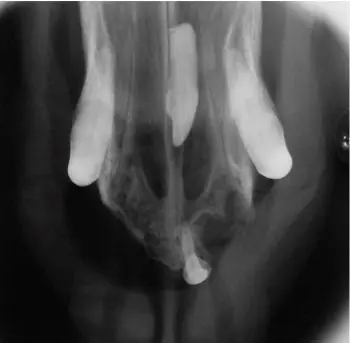

Figure 6. Dental radiograph of the left maxilla, showing an incisor displaced into the nasal passages during extraction.

Figure 7. A dorsal view of the same patient as in figure 6. Utilizing both views will help localize the location of the tooth for treatment planning.